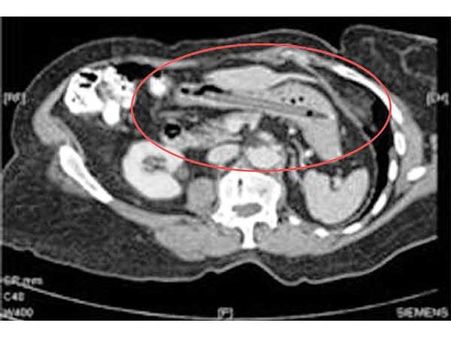

কাটাচামচের সেট

নেদাল্যান্ডের এক মহিলার পেটে ব্যাথার চিকিৎসা করতে গিয়ে তার পেটে এক্স-রে করে হতবাক ডাক্তাররাই। ওই মহিলার পেট থেকে মোট ৭২টি বিভিন্ন আকার আয়তনে চামচ কাটাচামচ পাওয়া গিয়েছে।